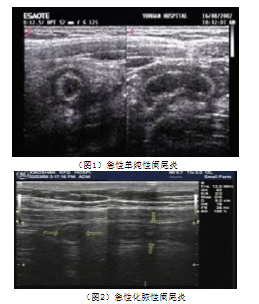

急性阑尾炎彩色多普勒超声影像图像特征及诊断

259x304 - 81KB - PNG

246x258 - 65KB - PNG